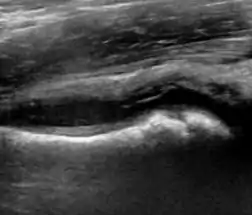

Ultrasound allows categorizing pediatric hips, according to Graf’s criteria, in four main types: normal, immature, and dysplastic (subluxed and dislocated). This classification is based on measurements of the acetabular inclination angle (alpha), cartilage roof angle (beta), and infant age. The femoral head coverage can also be determined by dividing the length of the femoral head covered by the acetabular fossa and the diameter of the femoral head. Its lower normal limits are 47% for boys and 44% for girls (Figure 11).[1]

Useful ultrasound measures in neonatal hip sonography, alpha and beta angles.[1]

Measurement of femoral head coverage.[1]